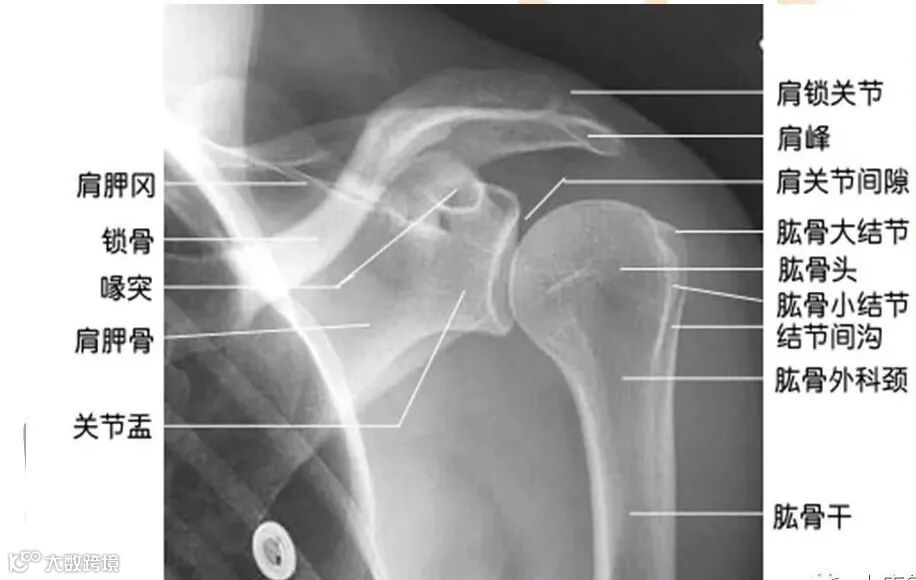

肩关节指上肢与躯干连接的部分,包括臂上部、腋窝、胸前区及肩胛骨所在的背部区域等身体很大的一部分。由肩胛骨关节盂和肱骨头构成,属球窝关节,是上肢最大、最灵活的关节。

一、肩肱关节